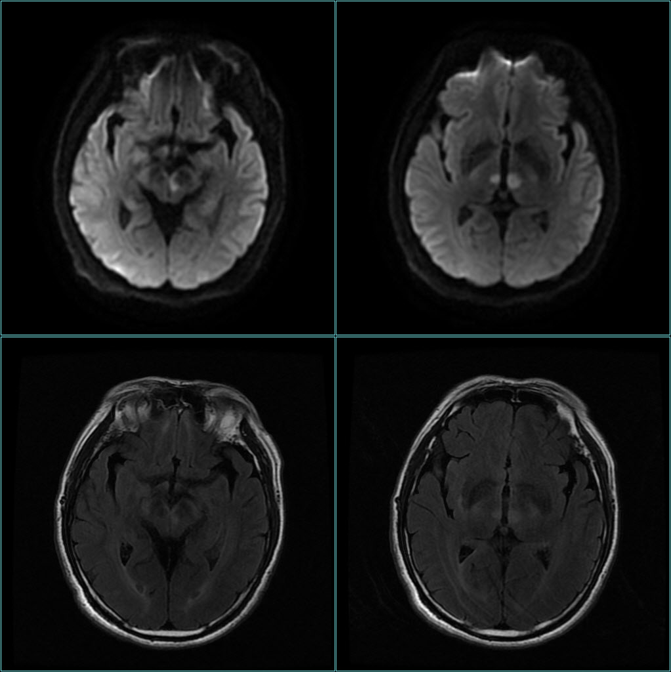

入院后行头颅磁共振示:1.中脑、双侧丘脑梗死;2.双侧脑实质多发缺血灶、软化灶;3.MRA示双侧大脑后动脉硬化样表现。

(图1.头颅MRI示中脑、双侧丘脑梗死)